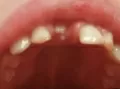

У нашей 5-летней дочери на нижней челюсти в районе центральных резцов с внутренней стороны видно, видимо, прорезывание постоянных резцов, небольшая припухлость. Резцы немного шатаются.

Нормально ли это? Я думал, что режущий край должен упереться в корень молочного и его вытолкнуть. А режущий край постоянного резца отстает во внутрь на несколько миллиметров.